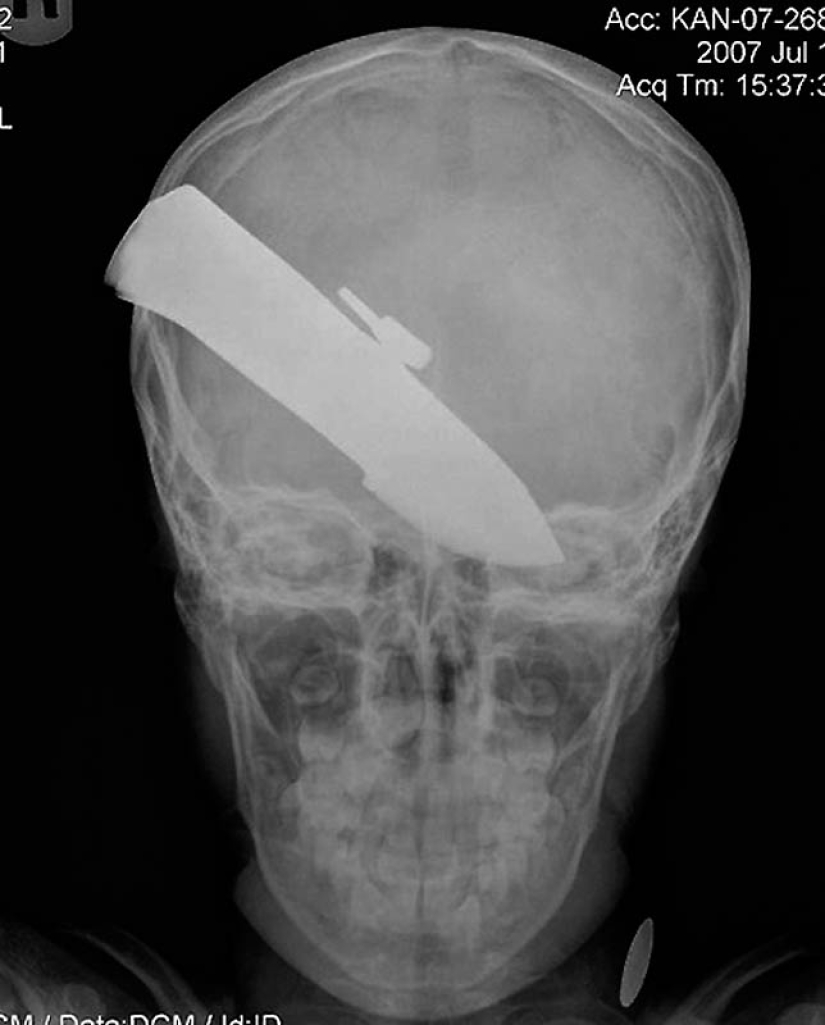

15. A knife in the head of a 10-year-old boy. The boy survived.

18. a 12-centimeter knife in the skull of a teenager.